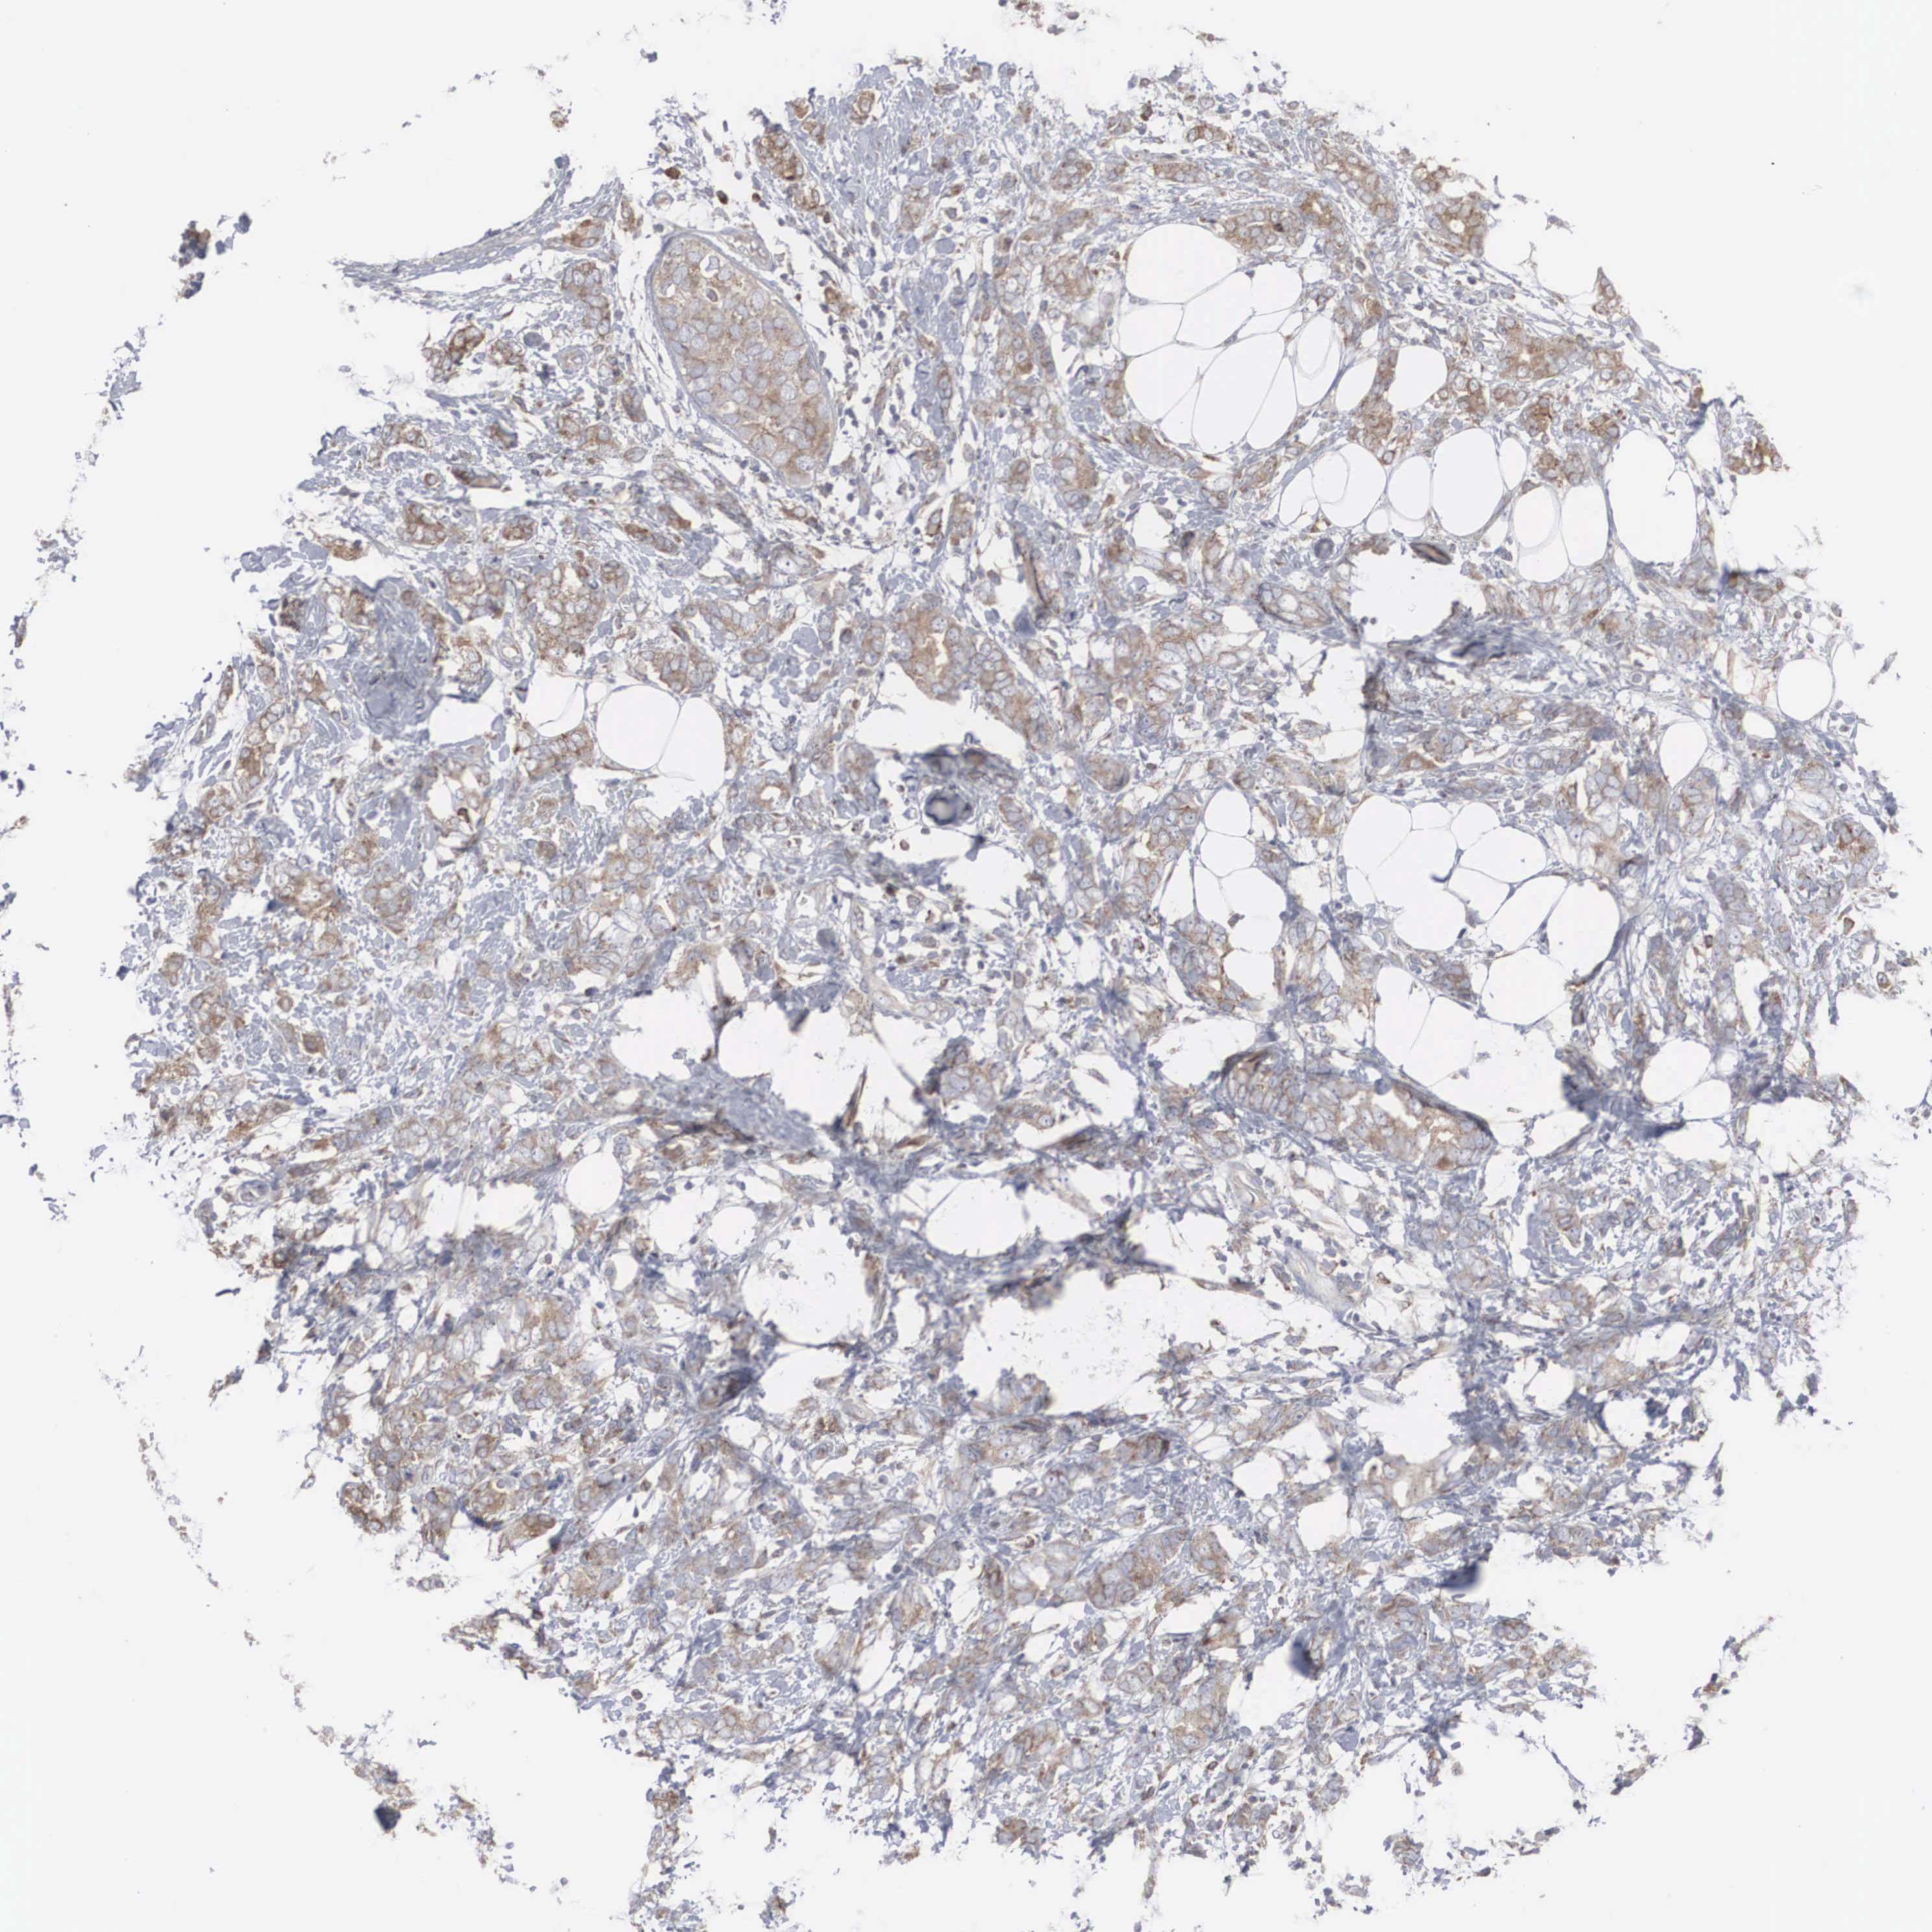

BREAST CANCER - Protein expressioni

A mouse-over function shows sample information and annotation data. Click on an image to view it in a full screen mode. Samples can be filtered based on level of antibody staining by selecting one or several of the following categories: high, medium, low and not detected. The assay and annotation is described here.

Note that samples used for immunohistochemistry by the Human Protein Atlas do not correspond to samples in the TCGA dataset.

Antibody stainingi

Antibody staining in the annotated cell types in the current human tissue is reported as not detected, low, medium, or high, based on conventional immunohistochemistry profiling in selected tissues. This score is based on the combination of the staining intensity and fraction of stained cells.

Each image is clickable and will lead to virtual microscopy that enables deeper exploration of all samples and also displays staining intensity scores, fraction scores and subcellular localization as well as patient and tissue information for each sample.

Antibody HPA000387

Antibody HPA000922

Staining

High

Medium

Low

Not detected

Intensity

Strong

Moderate

Weak

Negative

Quantity

>75%

75%-25%

<25%

None

Location

Nuclear

Cytoplasmic/membranous

Cytoplasmic/membranous,nuclear

Duct carcinoma

Lobular carcinoma

Neoplasm, malignant, NOS